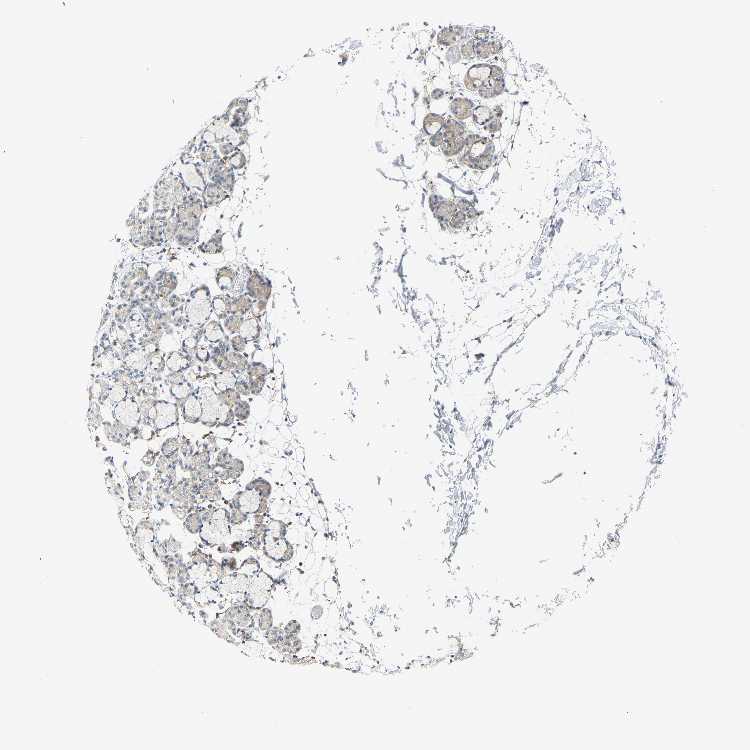

SALIVARY GLAND - Antibody stainingi

Antibody staining in the annotated cell types in the current human tissue is reported as not detected, low, medium, or high, based on conventional immunohistochemistry profiling in selected tissues. This score is based on the combination of the staining intensity and fraction of stained cells.

Each image is clickable and will lead to virtual microscopy that enables deeper exploration of all samples and also displays staining intensity scores, fraction scores and subcellular localization as well as patient and tissue information for each sample.

Antibody HPA016820Antibody HPA019887Antibody HPA032101

Glandular cells LowLowNot detected